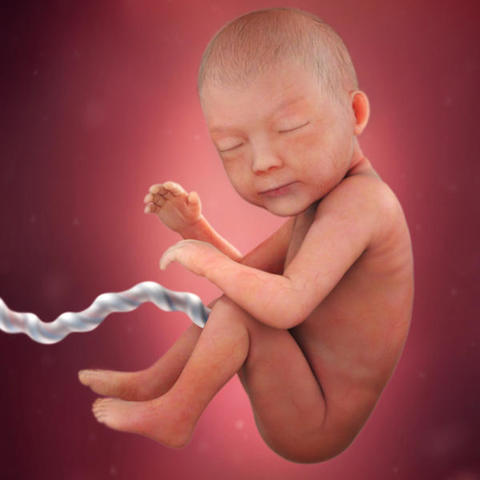

• SEMANA 35 A 38.PERIODO FINAL

SEMANA 35 A 38.PERIODO FINAL

Como el feto puede nacer en cualquier momento, el SNC lleva a cabo funciones de integración. 36 SEMANAS: el perímetro de la cabeza y el abdomen son simétricos. Hay una disminución de la velocidad de crecimiento. Ahora el tejido adiposo blanco constituye el 16% de la masa corporal. El tórax es prominente. Los testículos se localizan en el escroto.